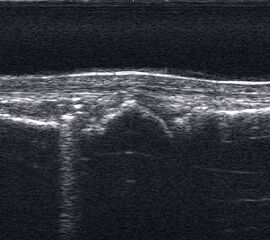

Ruptur Lig. fibulocalcaneare

Längsschnitt über dem Lig. fibulocalcaneare. Die Peronealsehnen erscheinen als echoreiche runde bis ovaläre Struktur.

Abbildung 19

Lagerung: Rückenlage, OSG in Neutralstellung.

Schnittebene: LS über Lig. fibulocalcaneare.

Referenzstrukturen: Fibulaspitze und Talus.

Befunde: Das Lig. fibulocalcaneare is nativ schlecht abgrenzbar, da es in die Tiefe und nicht parallel zum Schallkopf verläuft. Direkt über das Band ziehen quer getroffen die Peronäussehnen. Durch die Distorsion kann auch das Peritendineum peroneale einreißen. Die Peronealsehnen sind dann in ihrer Sehnenscheide von Blut umgeben, was sich als echoarmer Ring (Halo-Phänomen) darstellt und ein indirektes Zeichen für eine Verletzung des Lig. fibulocalcaneare ist.